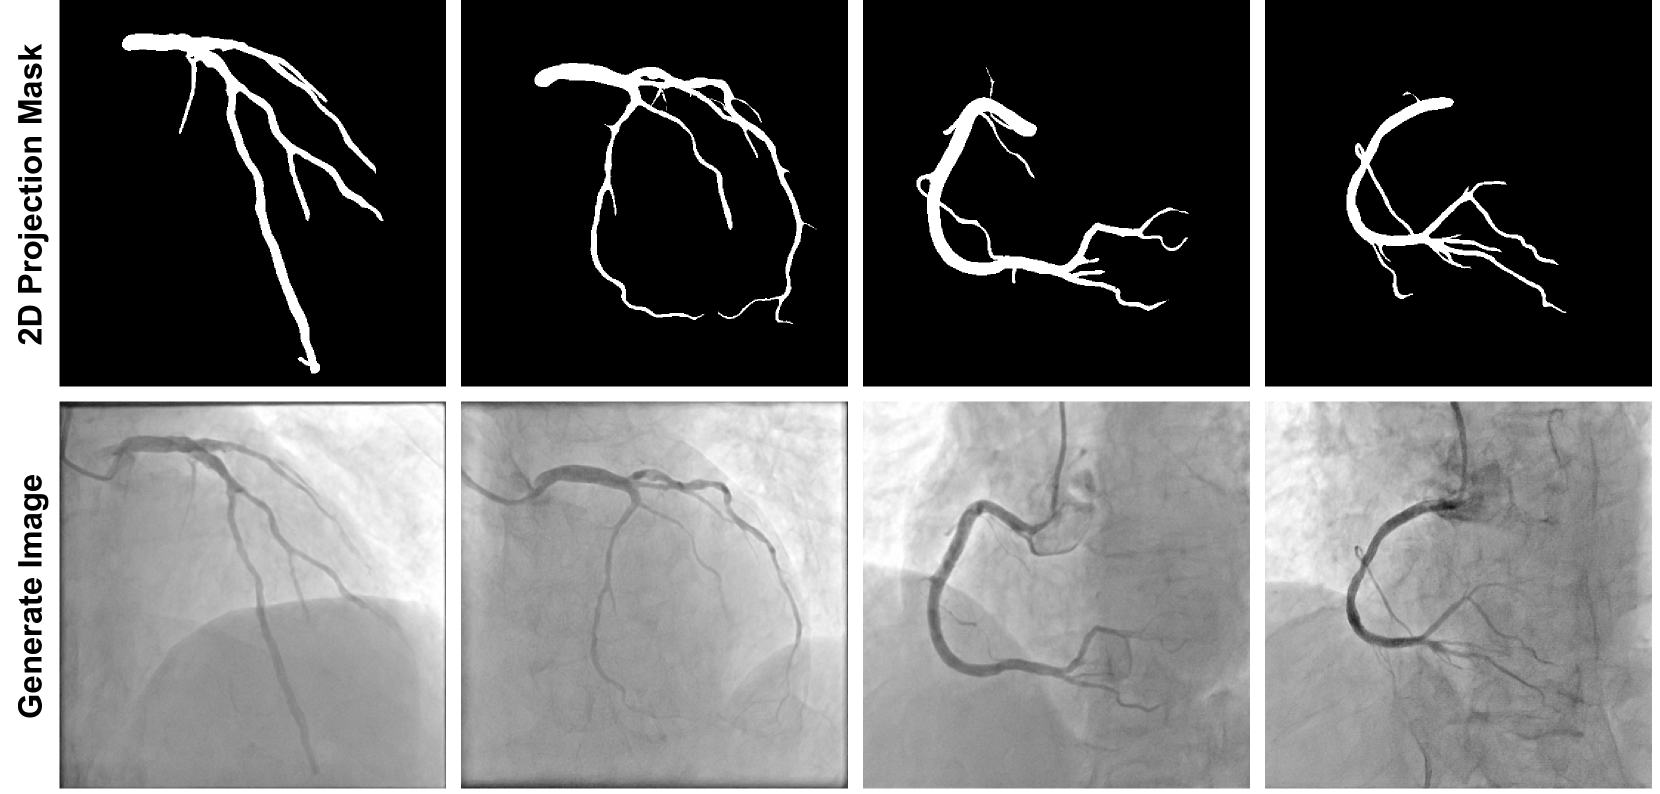

In this subsection, we qualitatively analyze the generation of synthetic data. In Figure 3, we randomly select two cases for the LCA and RCA. The first row shows masks projected from the 3D mesh, while the second row displays images generated by the trained IDDPM model. Overall, the generated images exhibit high quality, with realistic backgrounds and vessel contrast. The branches in the masks are all preserved in the generated images. However, compared to real images, the generated images lack some specific details, such as very small vessel branches, due to the resolution limitations of CTA images. Typically, CTA has lower resolution compared to DSA, which results in missing tiny structures like small vessels in both segmentation and reconstructed mesh. Our synthetic data generation is conditioned on the projection masks of the 3D mesh which also lack these details. So in the generated image, those small vessels are missing. Notably, even without specific labels for the catheter and its tip, the diffusion model learned to add the catheter at the inlet of the coronary artery and simulate the effect of contrast injection, enhancing the realism. This is because angiography imaging inherently includes the catheter for contrast injection, and the diffusion model implicitly learned this from the training dataset.

Refer to caption

Figure 3: Illustration of the masks and generated images from four randomly selected cases. The first row shows masks projected from the 3D mesh for the two LCA and two RCA cases, which are the condition for IDDPM model. The second row displays images generated by the trained IDDPM model.